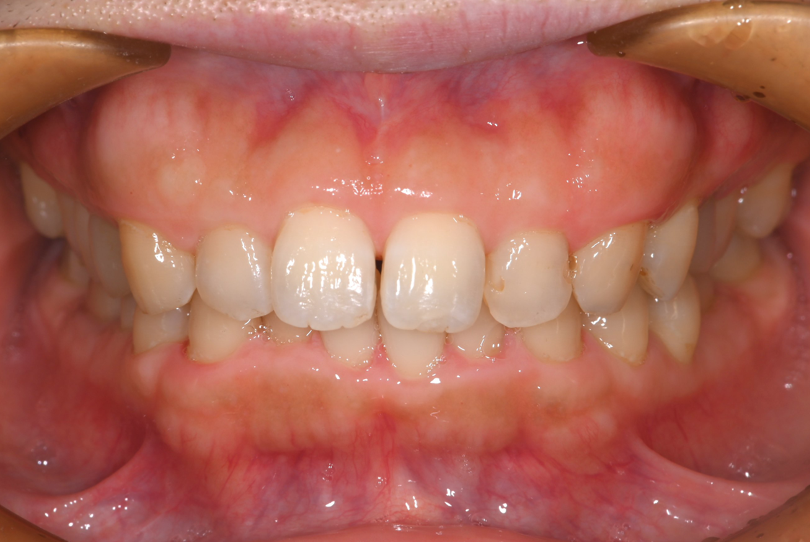

上下顎臼歯部にう蝕と全顎的な着色を認めたので、う蝕部位をE-maxで治療した後、PMTCによる着色除去を計画しました。

う蝕により黒くなっていた臼歯部はE-maxインレー(セラミックインレー)にて修復し、歯科衛生士によるPMTCで歯面に付着した着色を除去しました。

治療終了時、患者様には着色の無いきれいなご自身の歯に大変満足して頂きました。